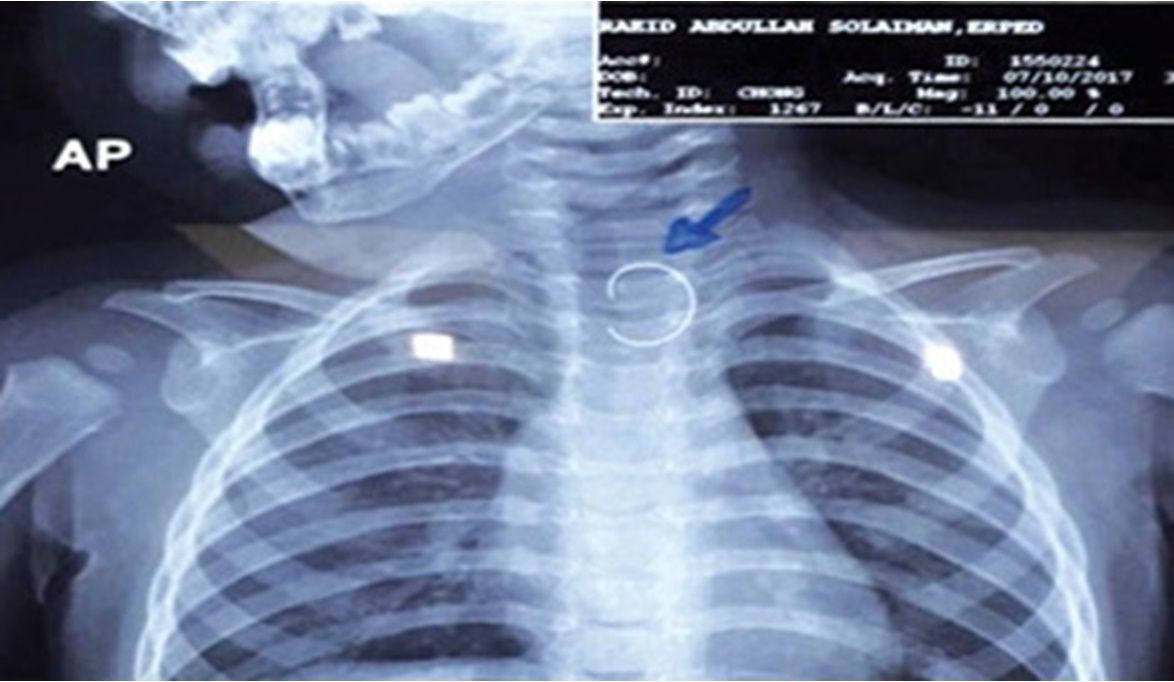

وأوضح الدكتور محمد متولي في مداخلة هاتفية لبرنامج "خط أحمر" الذي يقدمه الإعلامي محمد موسى على قناة الحدث اليوم، أن الأطفال في هذه السن غالبًا ما يبتلعون أي جسم يقع أمامهم، سواء كان طعامًا أو أشياء معدنية صغيرة، مضيفًا أن الطفلة بلعت دبوس المكتب الذي يثبت الأوراق، وظل عالقًا في جدار المريء، ما استدعى إجراء أشعة للتأكد من وجود الجسم الغريب قبل تجهيزها للعملية.

وأشار إلى أن خطورة الحالة كانت كبيرة، إذ كان الدبوس محاطًا بأنسجة المريء، وقد يؤدي أي خطأ إلى ثقب المريء، التهاب الصدر، أو الوفاة، وقال: "كنا نضع أيدينا على قلوبنا أثناء العملية حتى نخرج الدبوس بأمان".